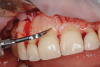

Fig 7. Osseous stage of crown lengthening procedure with CL guide.

Figure 7

The steps of the crown lengthening procedure were as follows: First, a gingivectomy was carried out to the planned gingival levels using electrosurgery along with a curette and chlorhexidine (CHX) pellets to clean the area (Figure 6). A full-thickness gingival flap was then raised using a 15c scalpel, followed by marking the bone level to the ideal biological width with a sterile surgical pencil and the surgical guide. Next, interproximal bone sculpting was done with a round diamond bur, and the osseous margins were refined to the marked levels using an ultrasonic tip, hand instruments, and limited rotary handpieces (Figure 7). Finally, the soft-tissue flaps were adapted with polypropylene sutures and a reverse cutting needle with a vertical mattress stitch.